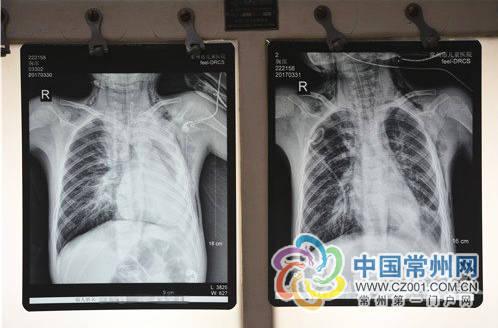

小儿支气管肺炎之常见症状

一般肺炎的临床表现按照起病的急缓程度,如果是突然发生的,可能会伴有发热、呕吐、烦躁等症状。上呼吸道感染可能再发病前已经持续数天,体温维持在38-39度左右。以下是几个典型的症状。